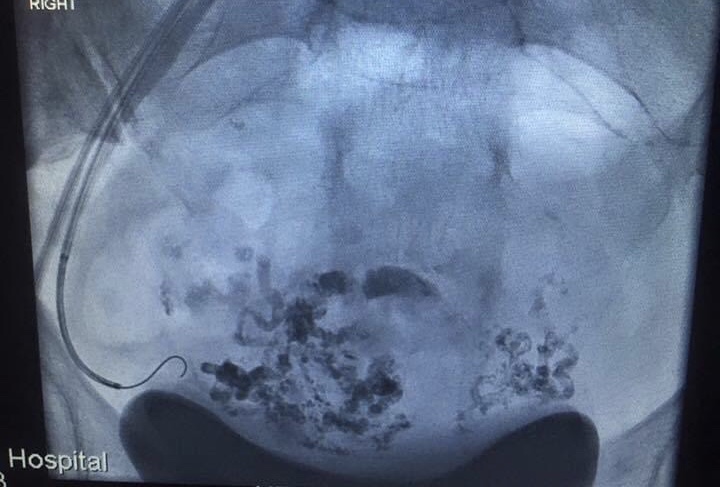

Here’s a shot of my uterine avm during embolization a cpl years ago. It was glued in May, and removed in November.